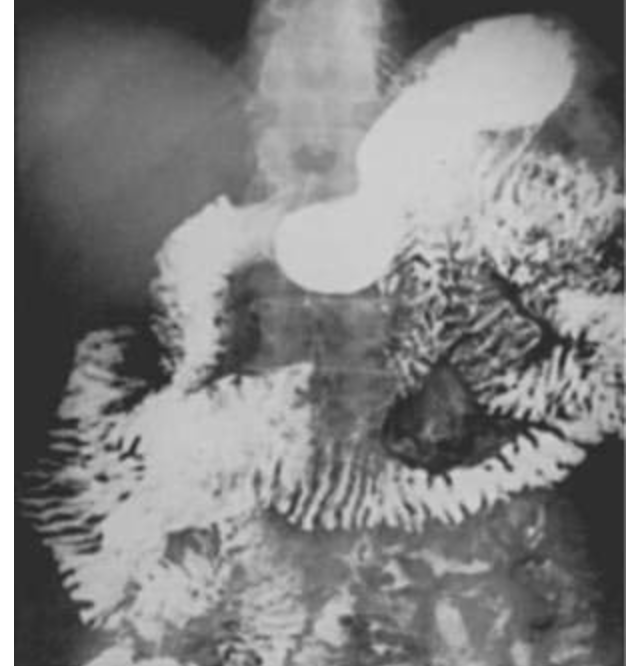

Hide-Bound sign of duodenum in scleroderma

The hide-bound bowel sign refers to an appearance on a barium study of the small bowel in patients with scleroderma. The sign describes the narrow separation between the valvulae conniventes which are of normal thickness despite dilatation of the bowel lumen.

Although the term hide-bound is used specifically to describe scleroderma, the same appearance may also be seen in sprue. The stack of coins sign, although similar, should not be confused with the hide-bound sign. The former is seen in intramural hematoma as adjacent, thickened folds with sharp demarcation and crowding of the valvulae conniventes.

The cause of hidebound appearance in scleroderma is thought to be asymmetric smooth muscle atrophy of the inner circular muscularis layer relative to the outer longitudinal layer. Contraction of the longitudinal layer results in foreshortening of the bowel and close packing of the valvulae conniventes.